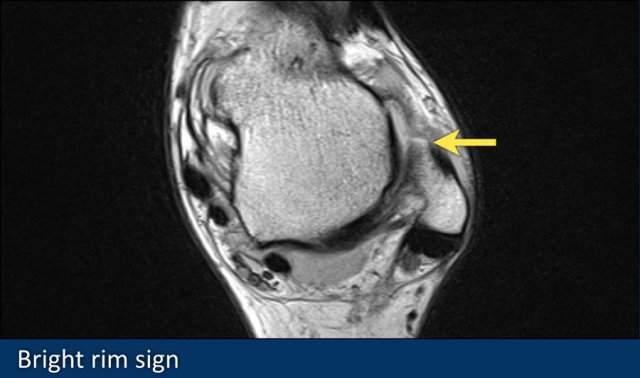

Bright rim sign

This sign presents as a fine linear band of high signal intensity which is the result of a small avulsion of cortical bone in a grade 3 full thickness tear.

Here an example of a grade 3 ATFL tear with a bright rim sign (arrow).

It is thought that it is caused by a chemical shift artifact when subcortical fatty marrow is exposed to joint fluid.